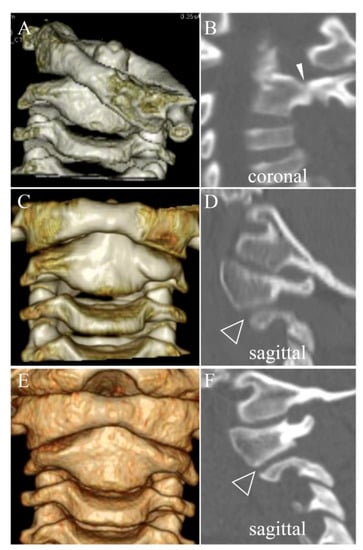

3.3. Direct Osseous Contact of the Facet Joint before and during Halo Fixation

4.1. Spontaneous Osseous Fusion after Halo Traction/Fixation

| SOF | Spontaneous Osseous Fusion of affected vertebrae which is confirmed after remodeling therapy for chronic AARF |

| DOC | Direct Osseous Contact of facet joints which is defined as disappearance of facet joint space between the adjacent vertebrae on sagittal or coronal CT images. |